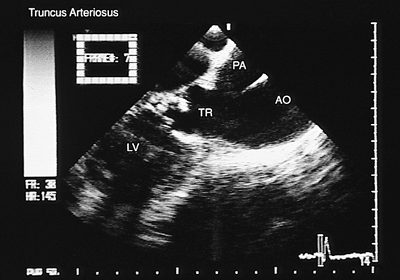

Truncus Arteriosus

When only one artery emerges from the heart, the V–A connection is defined as a single outlet. Three possibilities exist: truncus arteriosus, pulmonary atresia or aortic atresia. In truncus arteriosus, the vessel emerging from the heart originates the systemic, pulmonary, and coronary circulation. Images in the longitudinal plane obtained with a biplanar or multiplanar transducer show the truncus arteriosus straddling the interventricular septum (Fig. 8.2.57). The absence of right ventricular infundibulum is evident in transverse and longitudinal sections, and multiple images in both planes show the ventricular septal defect due to the absence of the infundibular septum. Transverse sections also show supernumerary truncal leaflets.

FIGURE 8.2.57. Truncus arteriosus. Images in the longitudinal plane confirm that the pulmonary artery (PA) originates from the posterior wall of the truncus arteriosus (TR). Dysplasia of the truncal valve can also be visualized. AO, aorta; LV, left ventricle.

FIGURE 8.2.58. Truncus arteriosus. Transverse plane image at the level of the common truncus arteriosus (TR) below the origin of the pulmonary circulation. LA, left atrium.

As the transducer is withdrawn to a plane slightly superior to the truncal valve, an attempt should be made to identify the emergence of the pulmonary artery or its branches from the posterior or lateral walls of the truncus arteriosus (Figs. 8.2.58 and 8.2.59).

FIGURE 8.2.59. Truncus arteriosus. The origin of the main pulmonary artery (MPA) and its branches, the right pulmonary artery and the left pulmonary artery (RPA, LPA), from the posterior portion of the common truncus arteriosus (TR) can be identified in images in the transverse plane.

FIGURE 8.2.60. Pulmonary atresia. Longitudinal plane view. Overriding of the aortic valve (AV) over the ventricular septum (VS) can be seen. AO, aorta; LA, left atrium; LV, left ventricle; RV, right ventricle.

Color Doppler aids in detecting stenosis or regurgitation of the truncal valve.